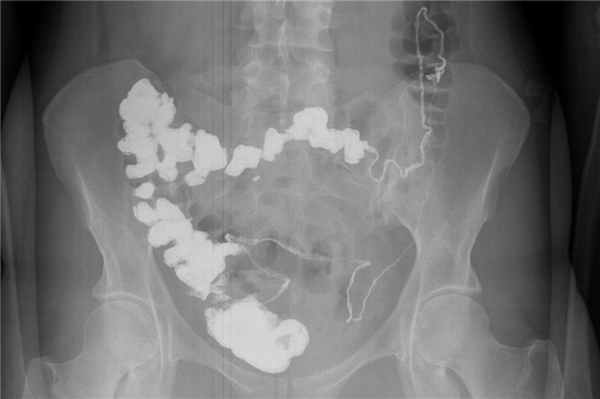

Рентгенограмма при катартической кишке

Пассаж бария по толстой кишке (со снимком)

Пассаж бария по кишечнику проводится при подозрении на кишечную необходимость, но перед процедурой следует исключить перфорацию (разрушение стенки с выходом воздуха) желудочно-кишечного тракта с помощью ФГДС. Пассаж с барием по кишечнику показывает: сужение просвета желудочно-кишечного тракта, затруднения его продвижения при блоке, кишечную непроходимость, тонкотолстокишечные свищи.

Методика предполагает пероральное (через рот) применение контрастного вещества и выполнение снимков через 1, 3, 6, 9, 12 и 24 часа. Через эти промежутки времени контраст продвигается в разные отделы желудочно-кишечного тракта: Через 1 час – контрастное вещество в тонком кишечнике. 3 часа – барий скапливается в области перехода между тонкой и толстой кишкой. 6 часов – начальные отделы восходящей ободочной кишки. 9 часов – поперечная и ободочная кишки. 12 часов – нисходящая ободочная и сигмовидная кишка. 24 часа – прямая кишка.

Пассаж бария (рентгенография пассажа бария) – это рентгенологическое исследование тонкого кишечника, которое позволяет увидеть общее состояние и моторно-эвакуаторную функцию тонкой кишки при помощи рентгеновских снимков. Данная часть полости живота (тонкая кишка)имеет много анатомических образований, изгибов, анатомических сужений, областей нарушенной моторики и секреторной активности, которые возможно визуализировать именно при этом исследовании. Чаще всего используется для выявления таких патологий как сужения кишечника, непроходимость или опухоли.